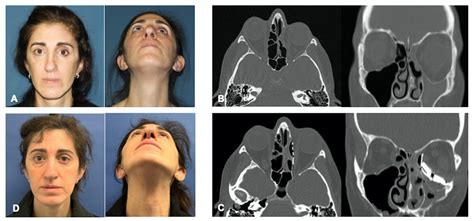

When you appear in the mirror, do you note a subtle dissymmetry in your expression that wasn't there before? Perhaps one eye appears slightly sunken or lower than the other, yet you sense no hurting or distinctive mark of infection. This peculiar set of symptoms is oftentimes the hallmark of Silent Sinus Syndrome (SSS), a rare but clinically significant condition that frequently fly under the radar. Unlike traditional sinusitis, which is characterize by intense facial pressure, discharge, and ague pain, this condition earns its name because it progresses stealthily, often without the patient realizing the fundamental structural changes occurring within their maxillary sinus.

Understood Sinus Syndrome, medically concern to as chronic maxillary atelectasis, imply the spontaneous collapse of the maxillary sinus wall. It typically affects only one side of the face. The process commence with the obstruction of the fistula ostium - the small opening that allows the fistula to drain and vent. When this gap becomes chronically blocked, the air inside the fistula is absorb by the mucosal lining, creating a negative pressing vacancy. Over clip, this void pulls the bony walls of the sinus inward, leading to a recognizable alteration in facial appearance.

• Enophthalmos: A obtrusive sinking of the eyeball into the orbit, caused by the retraction of the sinus roof (which function as the floor of the eye socket).

• Hypoglobus: The orb sit at a lower level than its counterpart, contributing to facial asymmetry.

• Facial Asymmetry: A flattening of the cheek area on the touched side.

Diagnose this stipulation postulate a specialized approach, as it is easy mistaken for other subject. Physician typically postdate a multi-step process to support the structural collapse. Tomography is the gold measure for diagnosing. A Computed Tomography (CT) scan will distinctly reveal the inward obeisance of the fistula wall, a atrophied fistula book, and the obstacle of the ostium. Below is a comparison of how this status differs from distinctive continuing sinusitis.